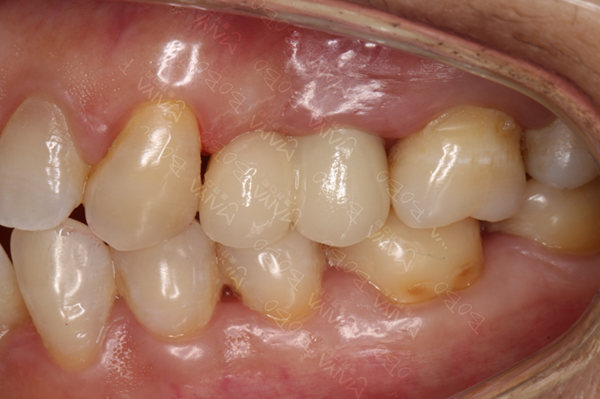

种植完成后的牙齿

种牙成功后口腔ct全景片